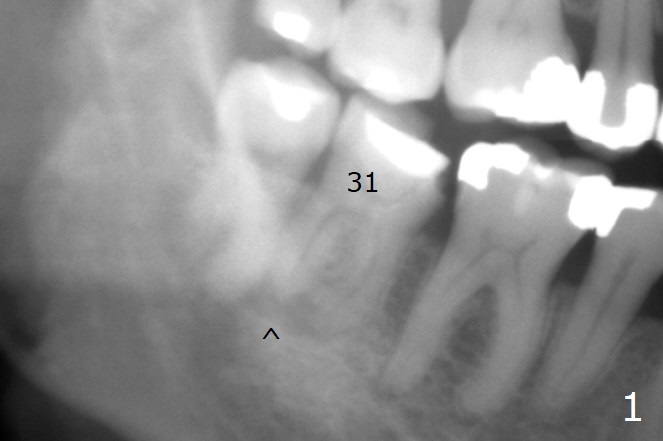

A 57-year-old skinny woman does not like dental X-ray or treatment.  After several years of delay, she agrees to have #31 extracted in the last day of Coronavirus Lockdown (Fig.1).  In addition to PARL (^), the buccal gingiva is recessive.  Take preop photos.  If the vein is thin, use GEM21S.  In fact it is the case.  GEM21S is chosen (I).